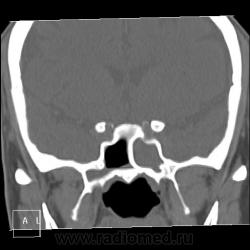

После пары менингитов на фоне синусита решили перебдеть. И вроде не зря... КТ: плотность содержимого в правой лобной пазухе 35-120 ед.Н. (мягкотканное с обызвествлением), в основной пазухе - 24 ед.Н (гнойной жидкости).

И пристеночный гайморит, и двусторонний этмоидит, и ринит, и односторонний сфеноидит, и фронтит, и очень тонкая костная пластинка между основанием передней черепной ямки и больной лобной пазухой - может быть реакция оболочек мозга...

По страшному снимку моему толком не видно, а вот на КТ множественные и разнообразные перегородки в пазухах видны хорошо. Я могу уверенно сказать только о следах жидкости в правой верхнечелюстной пазухе и субтотальном заполнении гомогенной жидкостью левой половины основной пазухи. Остальное, на мой взгляд, утолщение слизистой. Но на 100% утверждать не буду. В правой лобной я предполагаю (и только!) полипоз.

хр.фронтит: справа с образованием обызвествленных полипообразных образований,слева- в виде утолщения слизистой оболочки. Решетчатый лабиринт клиновидной кости занят патологическим содержимым жидкостной плотности(?) с обеих сторон. Основная пазуха: справа - пристеночное утолщение слизистой, слева - тотальное заполнение. Определяется утолщение слизистой верхнечелюстных пазух, видимо воспалительного характера.